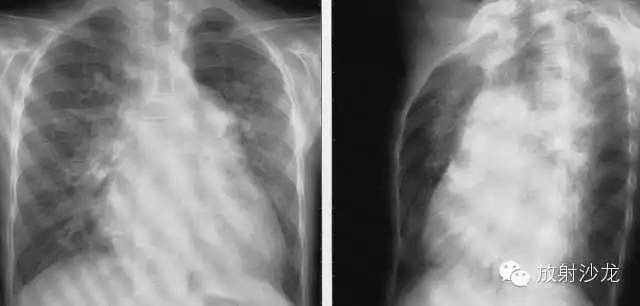

不同程度的左房增大

1、后前位:心尖左、下移位(胃泡内、越出锁骨中线)相反搏动点上移,左心缘延长、圆隆并向左下扩大。

2、左前斜位:心后缘向后下延伸与脊柱重叠,室间沟前下移。

3、侧位:食道前间隙消失,心后间隙变窄。